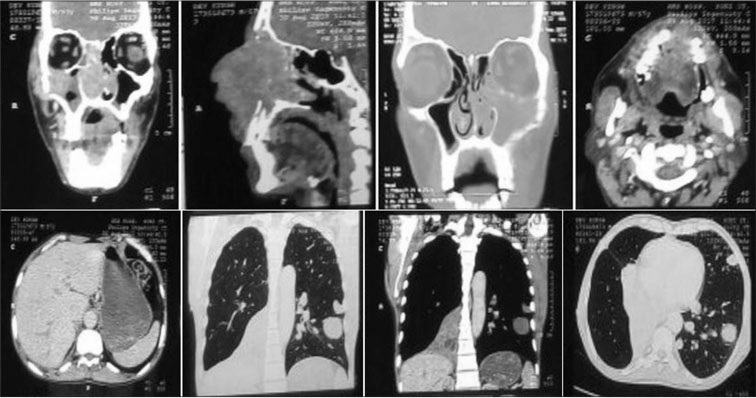

We herein report a case of a 56-year-old male, who presented to us with complaints of swelling over the nose associated with nasal blockade and discharge for past 1 year with increase in growth for past 3 months, swelling and pain in the left middle finger for past 3 months, and difficulty in breathing for past 1 month. The physical examination revealed swollen middle finger of left hand and exophytic mass replacing the nasal cavity [Figure 1]. The X-ray (anteroposterior and lateral views) of the left hand demonstrated lytic destruction of distal phalanx of middle finger [Figure 2]. The chest X-ray (posteroanterior view) demonstrated bilateral lung metastases [Figure 2], which was further confirmed by contrast-enhanced computed tomography (CECT) of thorax [Figure 3]. CECT of head and neck revealed an enhancing lesion in nasal cavity with the destruction of nasal cavity and extension into maxillary sinus and nasopharynx [Figure 3].

|?Figure. 3? Contrast-enhanced computed tomography of head and neck, thorax, and upper abdomen